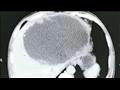

وذهب "شاي" إلى المستشفى بعد أربعة أشهر، عقب معاناته من قشعريرة وحمى شديدة لمدة ثلاثة أيام. وذهل الأطباء عندما اكتشفوا أن كبد المريض يحتوي على كتلة ضخمة مليئة بالصديد يبلغ طولها 19 سم وعرضها 18 سم، وفقا للتقرير.

وحاول الجراحون في البداية تقليل النتوء الاجتياحي مثل الكيس، عن طريق تجفيف الكتلة من السوائل، ولكنهم أدركوا بسرعة أن العدوى شديدة جدا، وقرروا قطع نصف الكبد.

وكشف فحص لاحق أن الكتلة كانت تحتوي على عدد لا يحصى من البيض الذي وضعه متفرع الخصية الصيني أو وشيعة الكبد الصينية، وهو طفيل موجود في المأكولات البحرية النيئة.